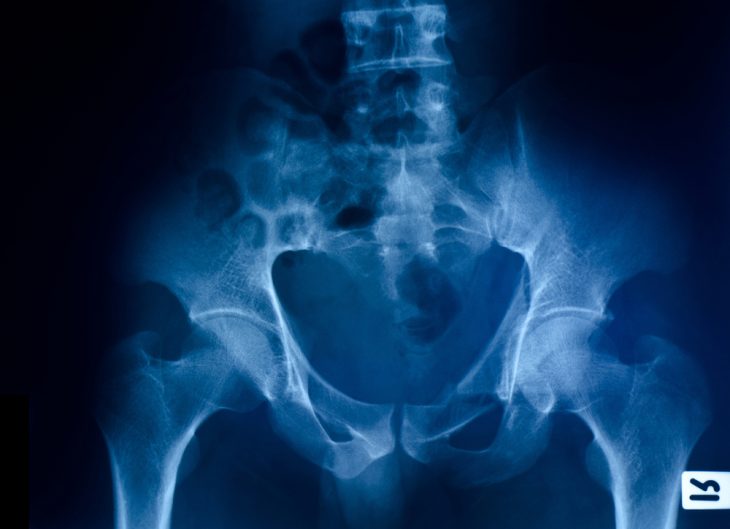

Таз – это система из нескольких соединенных между собой в кольцо костей, которые располагаются в основании позвоночного столба. Он является опорой для большей части скелета, связывает корпус тела и ноги и выполняет защитные функции для расположенных в нем внутренних органов.

Тазовое кольцо состоит из следующих костей:

- подвздошной;

- лонной;

- седалищной;

- крестца.

Кости тазового кольца соединены костными швами и неподвижны. Лонные кости впереди смыкаются и образуют лобковый симфиз, а подвздошные сзади прикрепляются к крестцу. С наружно-боковой стороны все тазовые кости участвуют в формировании части тазобедренного сустава – вертлужной впадины.

После осмотра и опроса пострадавшего травматолог назначает проведение рентгенографии. При необходимости рекомендуется выполнение КТ и/или МРТ.